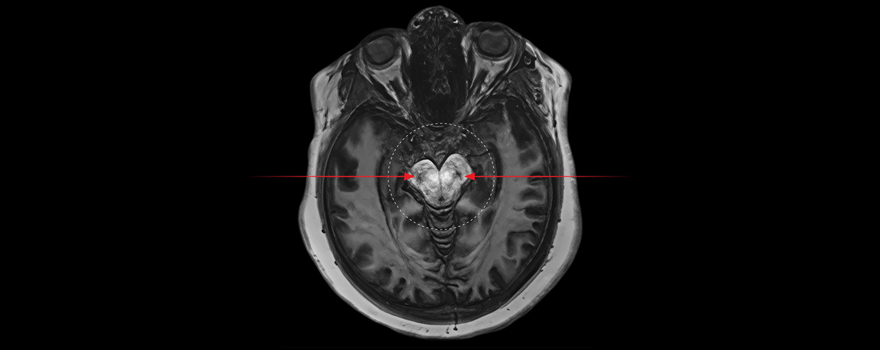

Using a non-invasive brain imaging technique called neuromelanin-sensitive magnetic resonance imaging, researchers were able to look at a substance called neuromelanin – a black pigment left behind in the brain that accumulates over time if there is too much dopamine. The neuromelanin appears in the scans as black spots, acting as a marker to measure and identify areas with dopamine activity.

“In people partaking in excess cannabis use, those spots are blacker than what they should be for their age compared to healthy individuals. This indicates they have high levels of dopamine, and in some cases are showing pigments someone 10 years older would have,” said Palaniyappan, who is also a professor at McGill University.

"We saw an increase of blacker spots in a particular region of the midbrain associated with psychosis – the substantia nigra and ventral tegmental areas. This increase was seen in those with cannabis use disorder regardless of whether they have first-episode schizophrenia,” said Ali Khan, PhD, associate professor in the Department of Medical Biophysics and scientist at Robarts Research Institute.